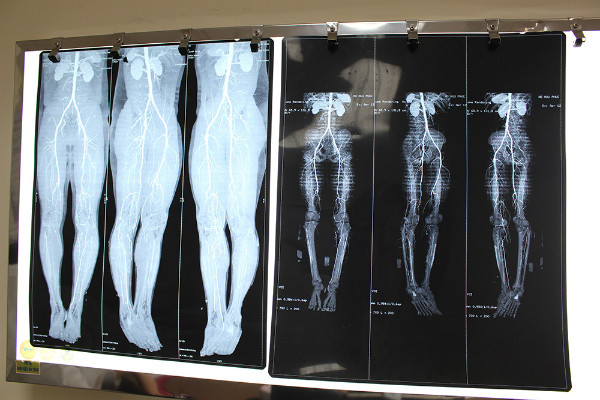

Kết quả chụp DSA cho thấy bệnh nhân đã tắc hoàn toàn các động mạch đùi nông, động mạch khoeo, động mạch chày trước và động mạch chày sau. Các bác sĩ quyết định dùng phương pháp nong động mạch bằng bóng, giúp tái thông các động mạch bị tắc.

| Phim X-quang tình trạng tắc động mạch chi dưới của bệnh nhân. |